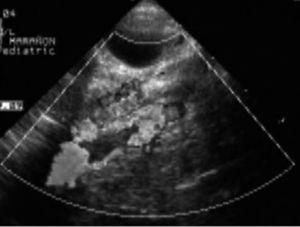

Se realizan las siguientes pruebas complementarias: radiografía de tórax donde se observa discreta cardiomegalia y signos de edema agudo de pulmón; ecografía abdominal (fig. 1) objetivándose un gran trombo que ocupa prácticamente toda la luz de la aorta abdominal desde la parte distal de la mesentérica superior hasta la bifurcación de ambas ilíacas. Ecografía transfontanelar: presencia de un trombo en el seno longitudinal superior, confirmado en la resonancia magnética (fig. 2) y en la angiografía cerebral (fig. 3) realizadas posteriormente.

Figura 1. Ecografía abdominal realizada a las 72 h del ingreso, donde se observa un gran trombo en la aorta abdominal.